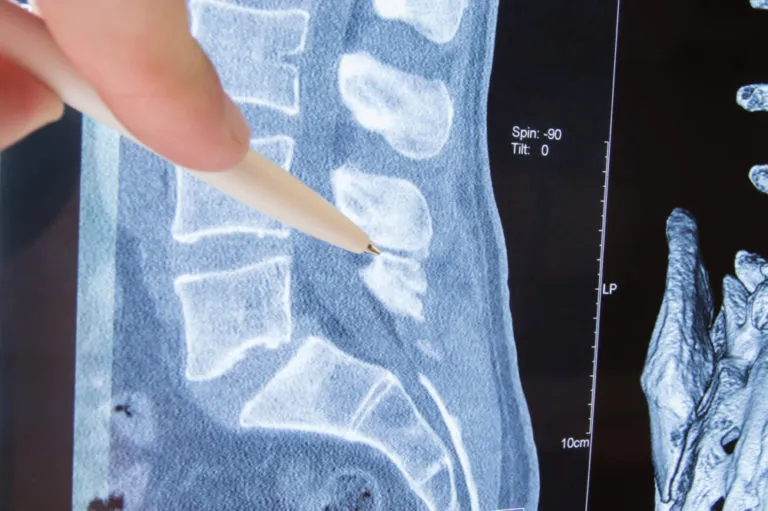

What is spinal stenosis? What can patients expect with this diagnosis? Are there treatment options? And, most importantly…does spinal stenosis go away? Living with a spine injury can cause complications to even the simplest daily tasks. If you’re dealing with undiagnosed symptoms, and you’re looking for a [spinal stenosis specialist in Los Angeles](https://dryashar.com/spine/cervical-lumbar-spinal-stenosis/), our professionals at Yashar Neurosurgery can provide some answers for you. Below, we’ll review the symptoms and treatment options of spinal stenosis, helping you to understand what to expect if you believe you are living with this condition. What Is Spinal Stenosis? In its official terms, spinal stenosis is defined as the way a body channel narrows more than it’s supposed to. This means that the spinal nerves or spinal cord can get squeezed tight within these bone channels, causing a lot of pain and sensitivity throughout different parts of the back. It can be a congenital condition, or it can develop over time. In most cases, it is a degenerative condition that develops over time within the spine. As you age, you may start to feel the effects of spinal stenosis more and more. What Are the Most Common Symptoms of Spinal Stenosis? Some patients compare spinal stenosis pain to the sciatica pain experienced in the gluteal region. These symptoms are described as: - Pain in the spine that comes and goes - Pain while walking or doing physical activities - Pain while holding the head up - Pain relief when sitting or lying down - Pain relief when bending forward Patients might also feel pain in the legs, as many nerves from the spine travel down to the back of the legs. It might hurt to walk, or to sit. There are different types of spinal stenosis that can determine the symptoms you might experience. Our spinal stenosis specialist in Los Angeles can schedule a one-on-one consultation with you to determine the type of spinal stenosis you are dealing with. What Are Some Spinal Stenosis Treatments? Can Spinal Stenosis Go Away? Thankfully, spinal stenosis can go away with proper treatment. There are a few different treatment options that our patients typically invest in to improve their mobility and reduce spinal pain: - Physical Therapy. This treatment involves a long-term plan to slowly strengthen your spine over time, naturally working your body to widen those narrowed bone gaps to free yourself of pain. This is not a cure, but it is a way to prevent debilitation. - Epidurals. Epidural injections are blasts of cortisone that can relieve the pain from spinal stenosis temporarily. Again, this is not a cure, but it can be used in cases of severe pain to prevent the symptoms from becoming overwhelming. - Medication Treatments. Your doctor may prescribe ibuprofen or aspirin as an anti-inflammatory measure to reduce the pain of your symptoms. However, this is not a good long-term plan, as ibuprofen can damage the kidneys over time. - Surgery. Often used as a last resort, spinal stenosis surgery is used to identify the source of the narrowed bone channels and possibly correct them. This is mostly an exploratory surgery that does not guarantee complete relief from the condition. However, it may be used to aid your personal situation. One of the most successful ways to reduce pain and symptoms from spinal stenosis is to invest in activity modification. Changing the way you move, exercise, sit, and sleep can have drastic results on the pressures placed upon your spine. You may need to learn how to cope with your narrowed bone channels, only moving your body in ways that will prevent a flare-up of pain. Get A Spinal Stenosis Consultation ASAP! When it comes to spine injuries, it’s dangerous to wait without seeing a doctor. Our spinal stenosis specialist in Los Angeles can schedule a consultation with you to get your pain assessed right away. Yashar Neurosurgery specializes in spinal injuries and pain, and we can provide a customized treatment plan to fit your needs. For more information, [contact us online](https://dryashar.com/contact-us/) or give us a call at (424) 361-0923. Don’t wait until it’s too late!